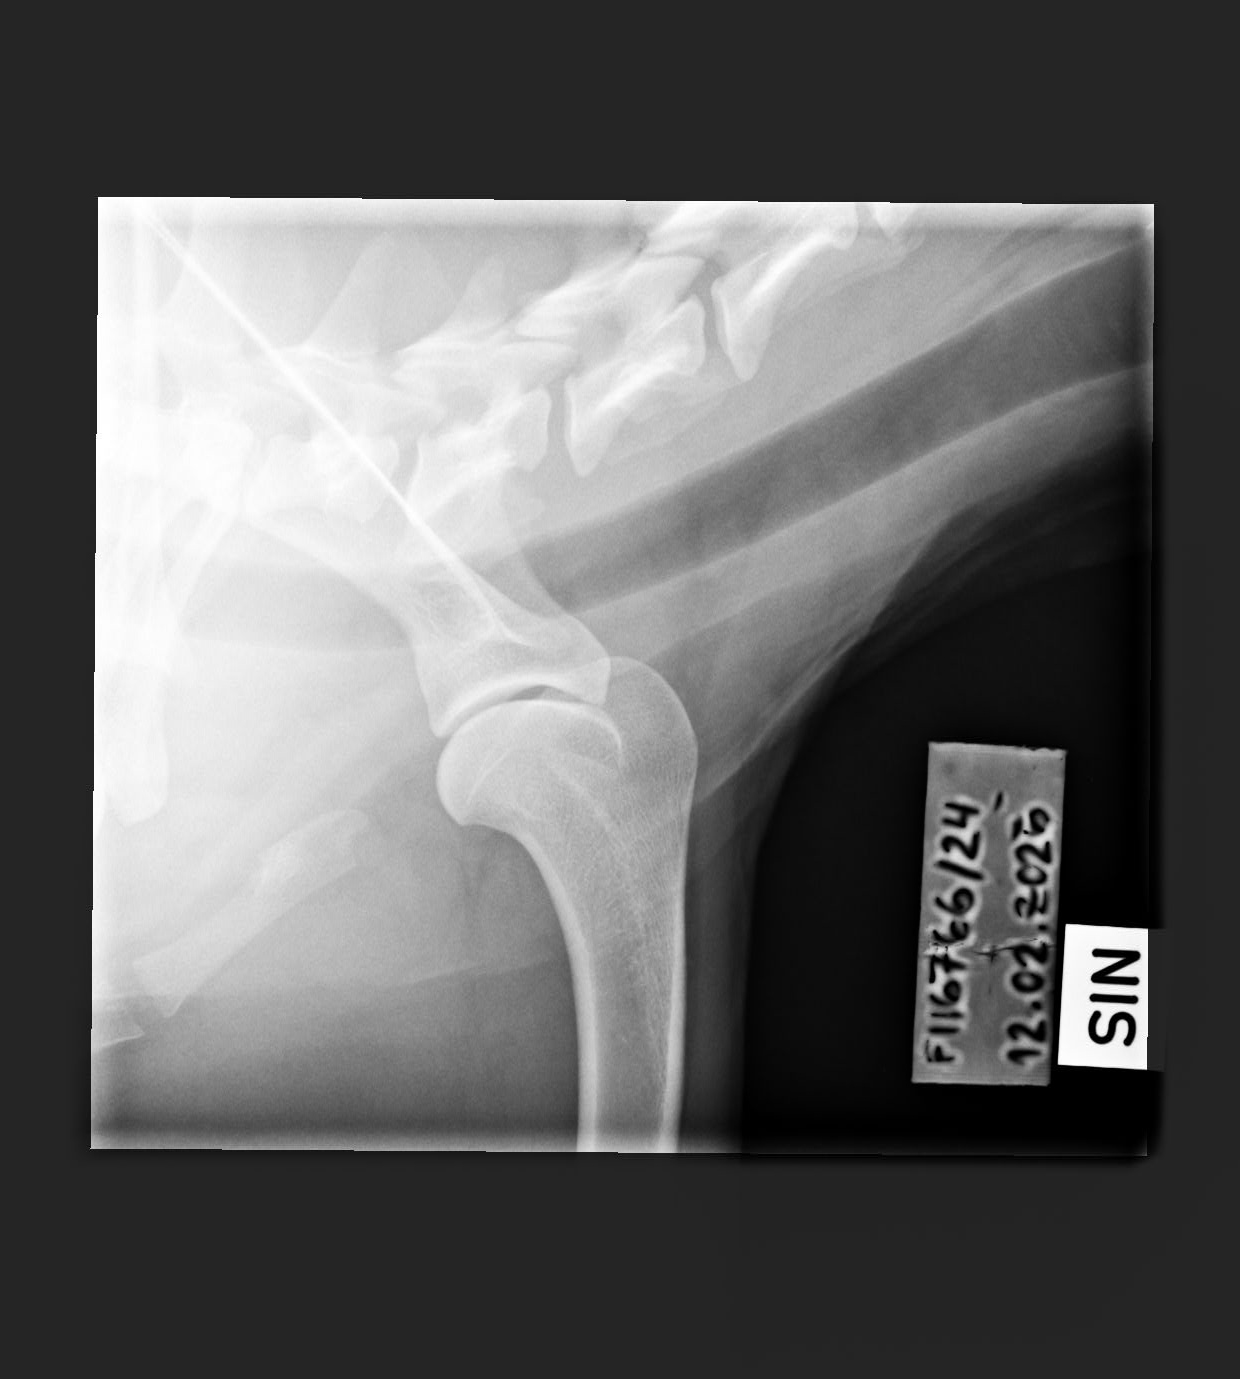

0/0 (CT - report in Finnish only) |

- Elbow x-rays '11: left/right

- Elbow x-rays '12: left/right